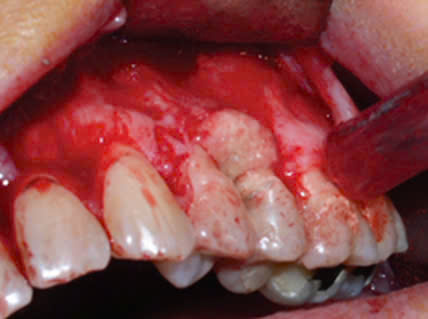

– Trong nha khoa, việc sử dụng arsenic có thể gây những biến chứng như: Hoại tử xương hàm; Hoại tử mô mềm, hoại tử lợi; Viêm tủy xương hàm…

Hình 1: Hoại tử xương hàm ở vị trí răng 46 sau điều trị nội nha có sử dụng Arsenic5

Điểm chung của những ca lâm sàng này là bệnh nhân sử dụng arsenic trong điều trị tủy để giảm đau nhưng khi ra về bệnh nhân gặp phải cơn đau dữ dội và phải quay lại phòng khám để nhổ răng. Tuy nhiên, tình trạng tổn thương đã lan ra ngoài xương hàm.